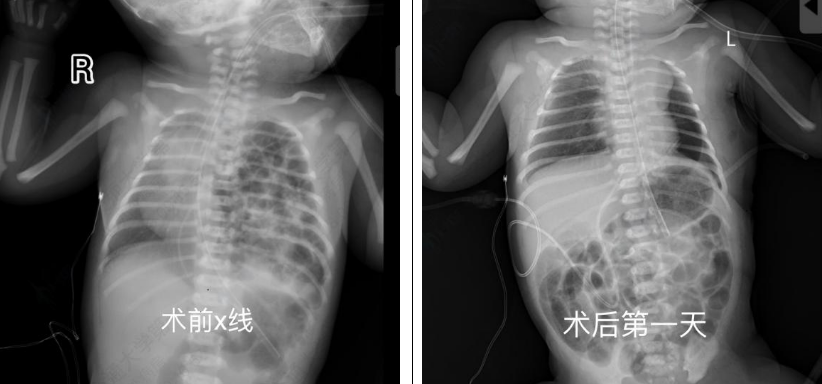

患儿出生后即刻出现呼吸困难,新生儿科团队第一时间实施气管插管建立通气,迅速稳定氧饱和度。转入新生儿重症监护室后,医护团队24小时值守监测,为手术创造条件。出生满24小时,经综合评估及指南依据,儿外科团队决定实施胸腔镜下膈疝修补术。术中可见脾脏、肠管已占据患儿整个胸腔,曹振杰主任团队在狭小空间内精细操作,将脏器逐一还纳,并用生物补片修补巨大膈肌缺损,麻醉科与护理团队全程精密配合,手术顺利完成。